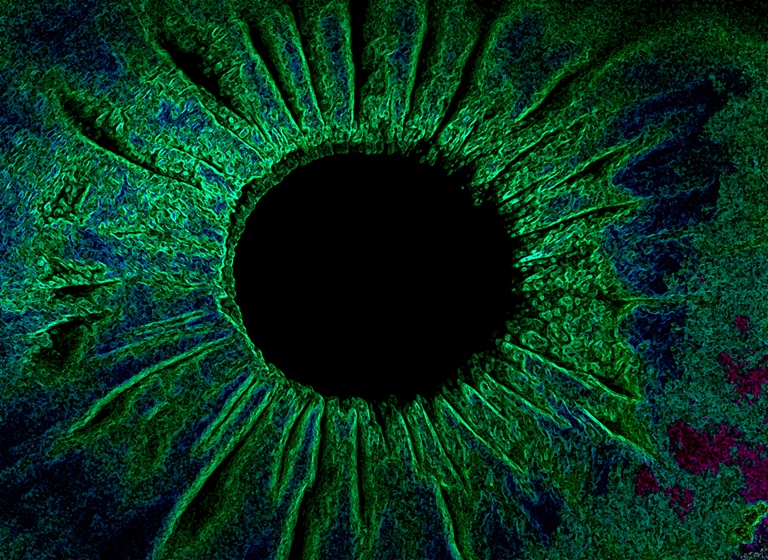

Iris Watercolor

Presented by Denice Barsness, BA, CRA, COMT, ROUBThis photograph received 2nd Place in the category "The Eye as Art" and was displayed at the 2024 ASCRS/OPS Society Exhibit.